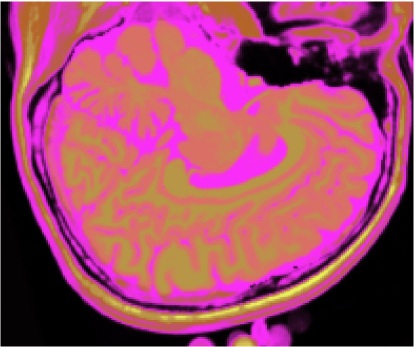

A figura 6 mostra os resultados de classificação, enquanto a figura 7 exibe os resultados de quantização para a imagem sem ruído da fatia 97, figura 5, usando os métodos KO, CM, KM, ODC-PME e ODC-CAN. Esses resultados ilustram qualitativamente as diferenças entre os métodos de classificação e quantização, dado que a fatia 97 possui todas as 13 classes presentes na análise [51].

Figura 6: Composição colorida R0-G1-B2 das imagens da fatia 97 ponderadas em PD, T1subscript𝑇1T_{1} e T2subscript𝑇2T_{2} (a) e resultados de classificação usando os métodos KO (b), CM (c), KM (d), ODC-PME (e) e ODC-CAN (f)

A tabela 2 mostra os resultados da avaliação dos métodos de classificação não supervisionada quanto à quantização vetorial, usando os índices de fidelidade ϵMEsubscriptitalic-ϵME\epsilon_{\textnormal{ME}}, ϵMAEsubscriptitalic-ϵMAE\epsilon_{\textnormal{MAE}}, ϵMSEsubscriptitalic-ϵMSE\epsilon_{\textnormal{MSE}}, ϵRMSEsubscriptitalic-ϵRMSE\epsilon_{\textnormal{RMSE}} e ϵPSNRsubscriptitalic-ϵPSNR\epsilon_{\textnormal{PSNR}}, considerando todas as 181 fatias com 3 bandas (DP, T1subscript𝑇1T_{1} and T2subscript𝑇2T_{2}), para os métodos KO, CM, KM, ODC-PME e ODC-CAN e 0% de ruído. Já os gráficos das figuras 8, 9, 10 e 11 mostram os resultados em função do nível percentual de ruído para os diversos métodos, para um total de 6 volumes de 181 fatias de 3 bandas, totalizando 1086 imagens coloridas, ou 3258 imagens em níveis de cinza.

Figura 7: Composição colorida R0-G1-B2 das imagens da fatia 97 ponderadas em PD, T1subscript𝑇1T_{1} e T2subscript𝑇2T_{2} (a) e resultados de quantização usando os métodos KO (b), CM (c), KM (d), ODC-PME (e) e ODC-CAN (f)